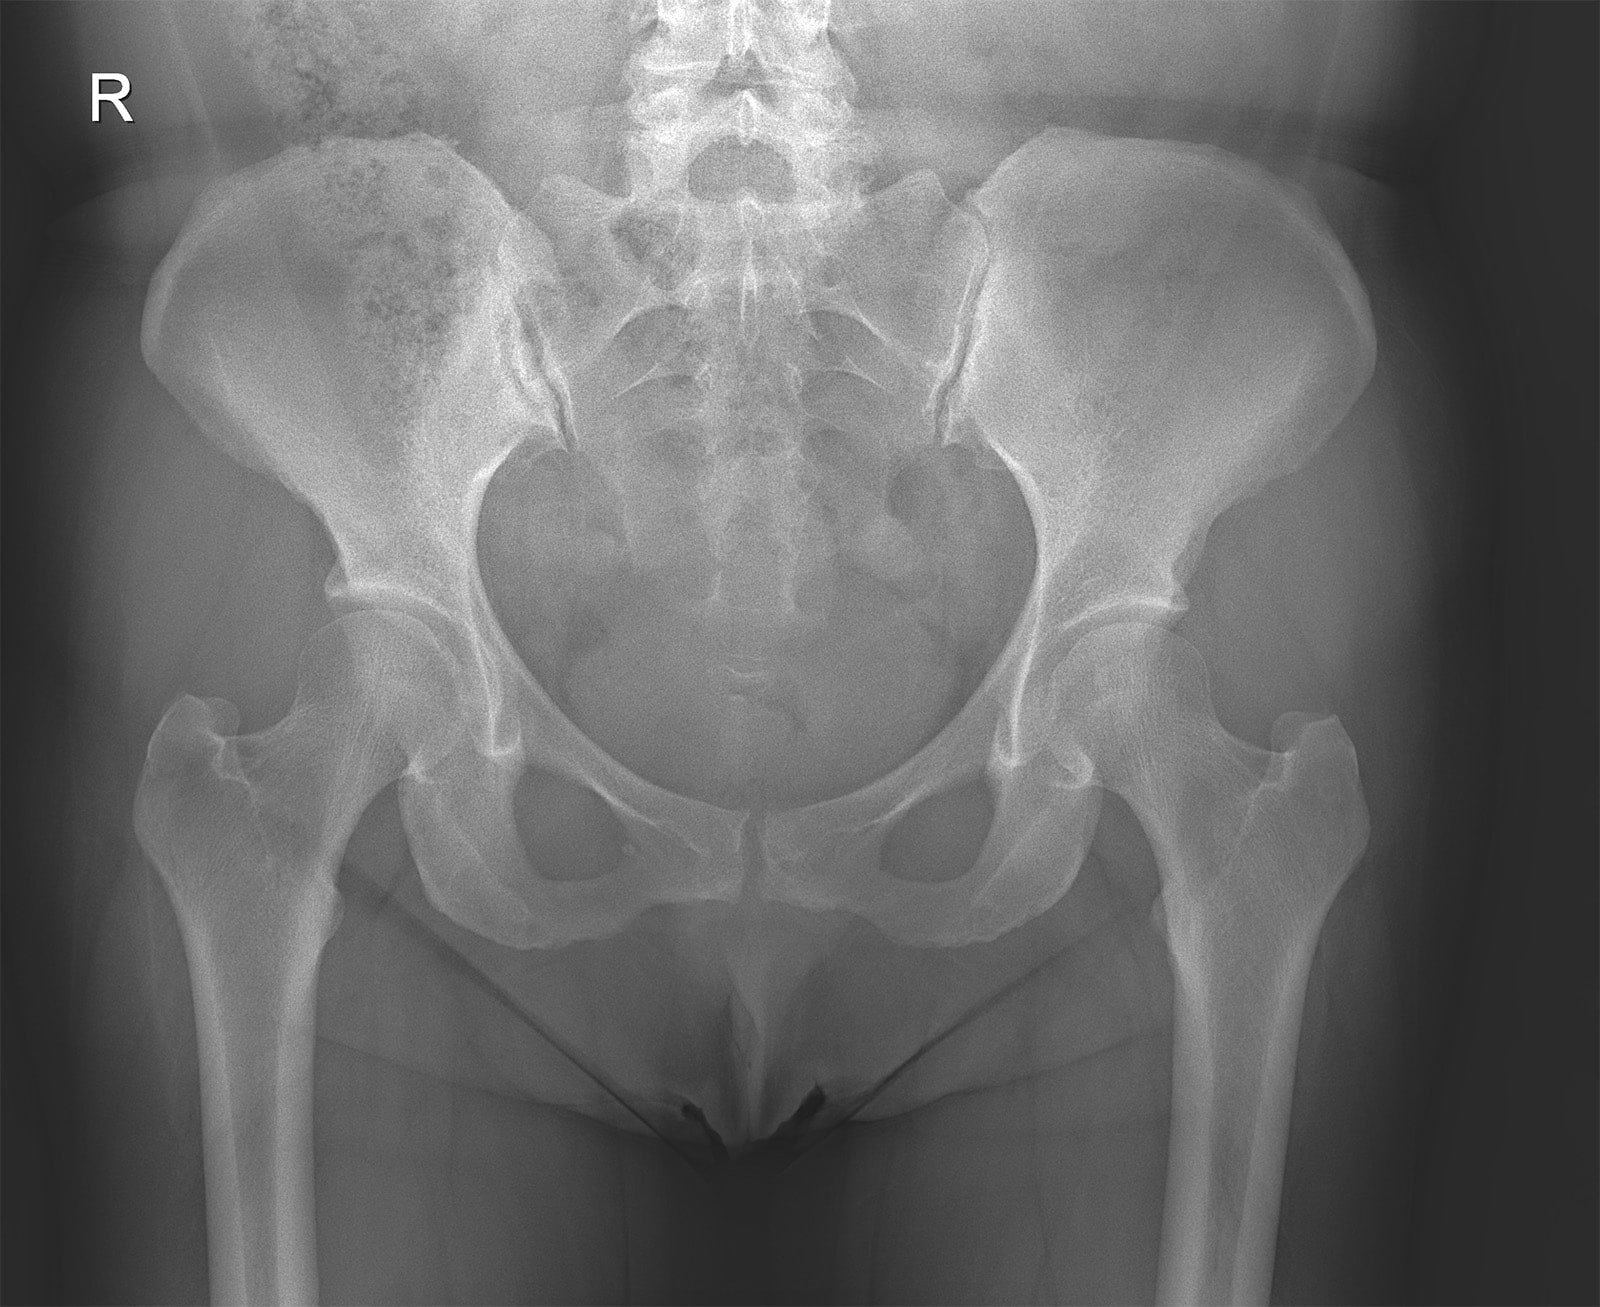

Рентгенография (Рентген) - метод лучевой диагностики, позволяющий получить изображения любой части тела. Пациент становится у стойки аппарата или располагается на специальном столе. Длительность исследования - несколько секунд. Оборудование низкодозное (0,02-0,04 мЗв) и безопасно для здоровья пациентов, в том числе для детей. Флюорография проводится методом цифровой рентгенографии с высоким разрешением, при этом лучевая нагрузка ниже в десять раз, чем при обычной флюорографии.

Рентген от производителя Siemens (Германия) позволяет получать изображения любой части тела. Включает в себя инновационные технологии, реализуемые в экспертных рентгеновских установках, что обеспечивает высокое качество изображения.

Данный рентгеновский аппарат является низкодозным, что особенно важно при обследовании детей.